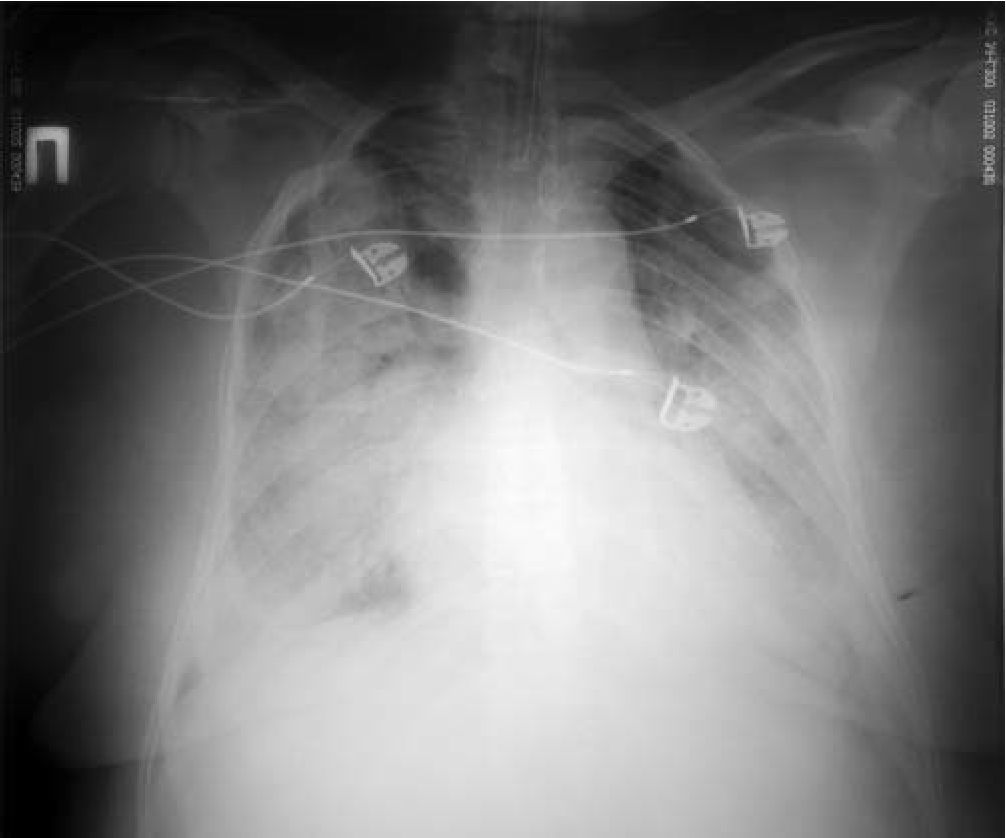

При рентгенографии в условиях ИВЛ выявлена интенсивная инфильтрация легочной

ткани во всех отделах легких с небольшой зоной сохранившейся пневматизации в верхних зонах, корни не визуализируются. Сердце расширено в поперечнике (рис. 1).

Рис. 1. Двусторонняя инфильтрация лёгочной ткани.